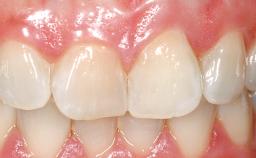

Immediate Flapless Placement of an Implant in a Maxillary Left Central Incisor Site

A 42-year-old female patient was referred to our clinic at the School of Dentistry of the University of São Paulo in November 2004, presenting a deficient restoration in the upper left central incisor. The clinical examination revealed no gingival retraction or any signs of gingival inflammation and, therefore, previous periodontal treatment was not considered. The patient presented a high lip line at full smile and a thin tissue biotype. This combination characterized a high-risk situation from an anatomic point of view, which required careful preoperative planning and cautious surgical execution.

Loading Protocol Immediate

Mesio-Distal Space Symmetry +/- 1 mm of contra-lateral tooth

Provisional Implant-Supported Prosthesis Prosthodontic margin < 3 mm apical to mucosal margin Prosthodontic margin < 3 mm apical to mucosal margin